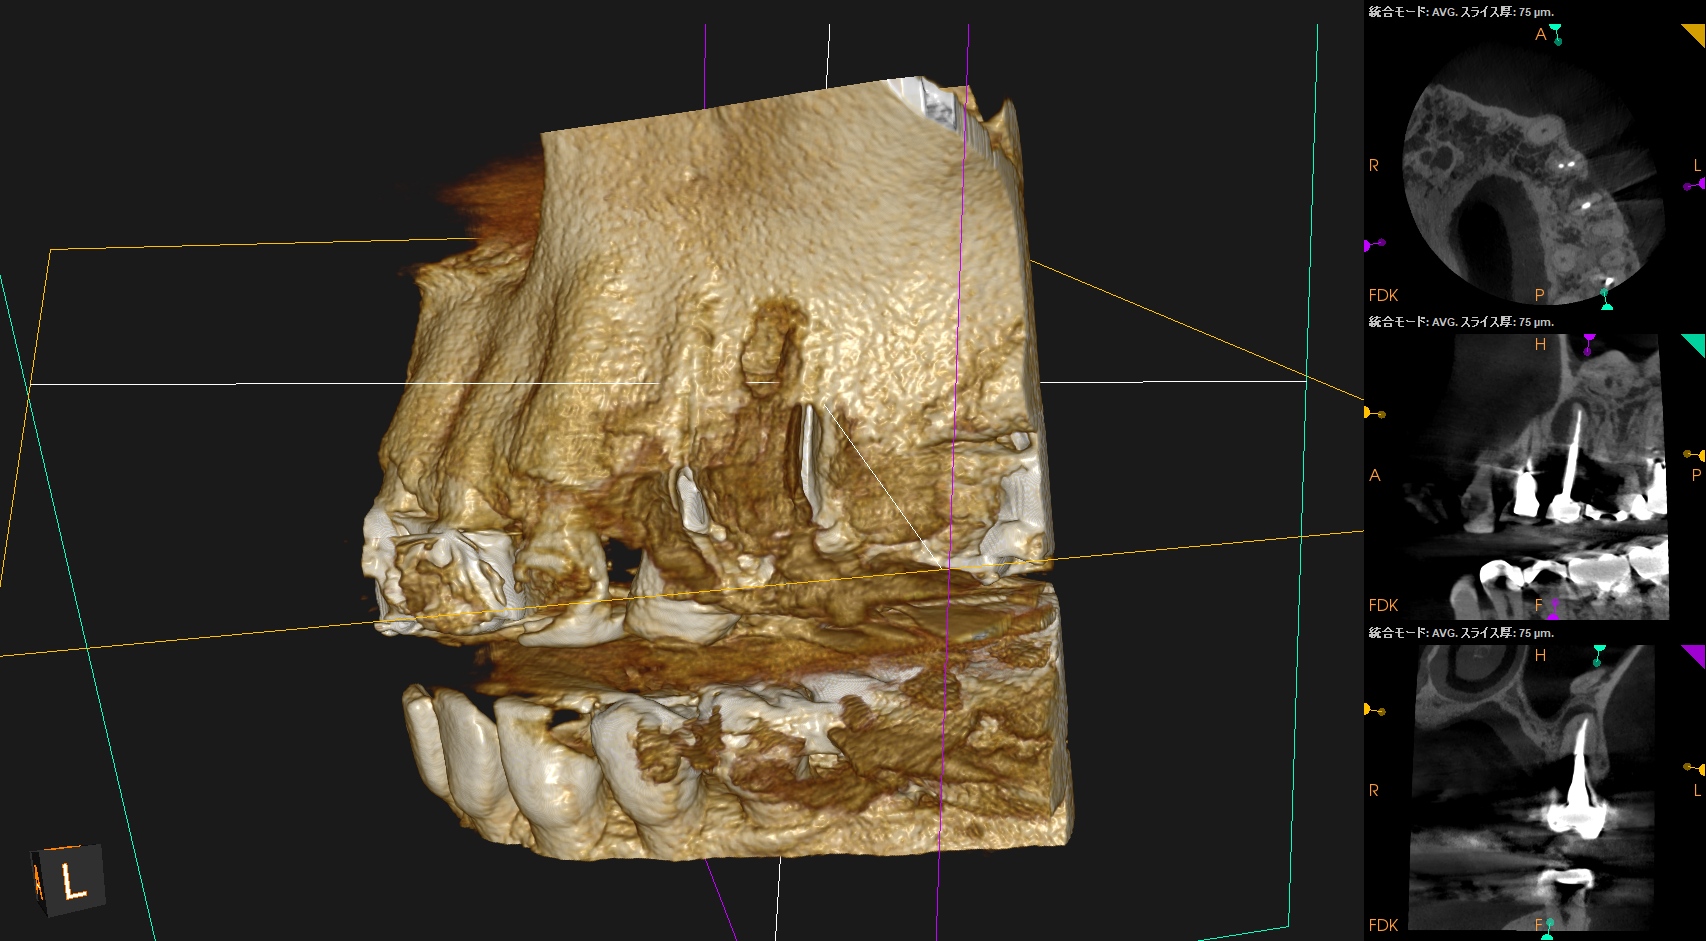

CBCT(2025.8.25)

#12 B

#12 P

#13

外科治療の際は、

上記のように行う必要がある。

これは中程度の難易度だろう。